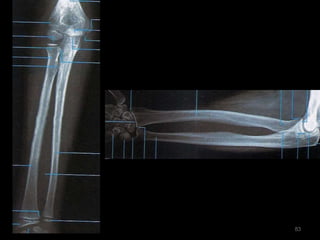

Incidência AP/PA do antebraço81

82

83

Incidência lateral do antebraço: látero-medial84

85

86